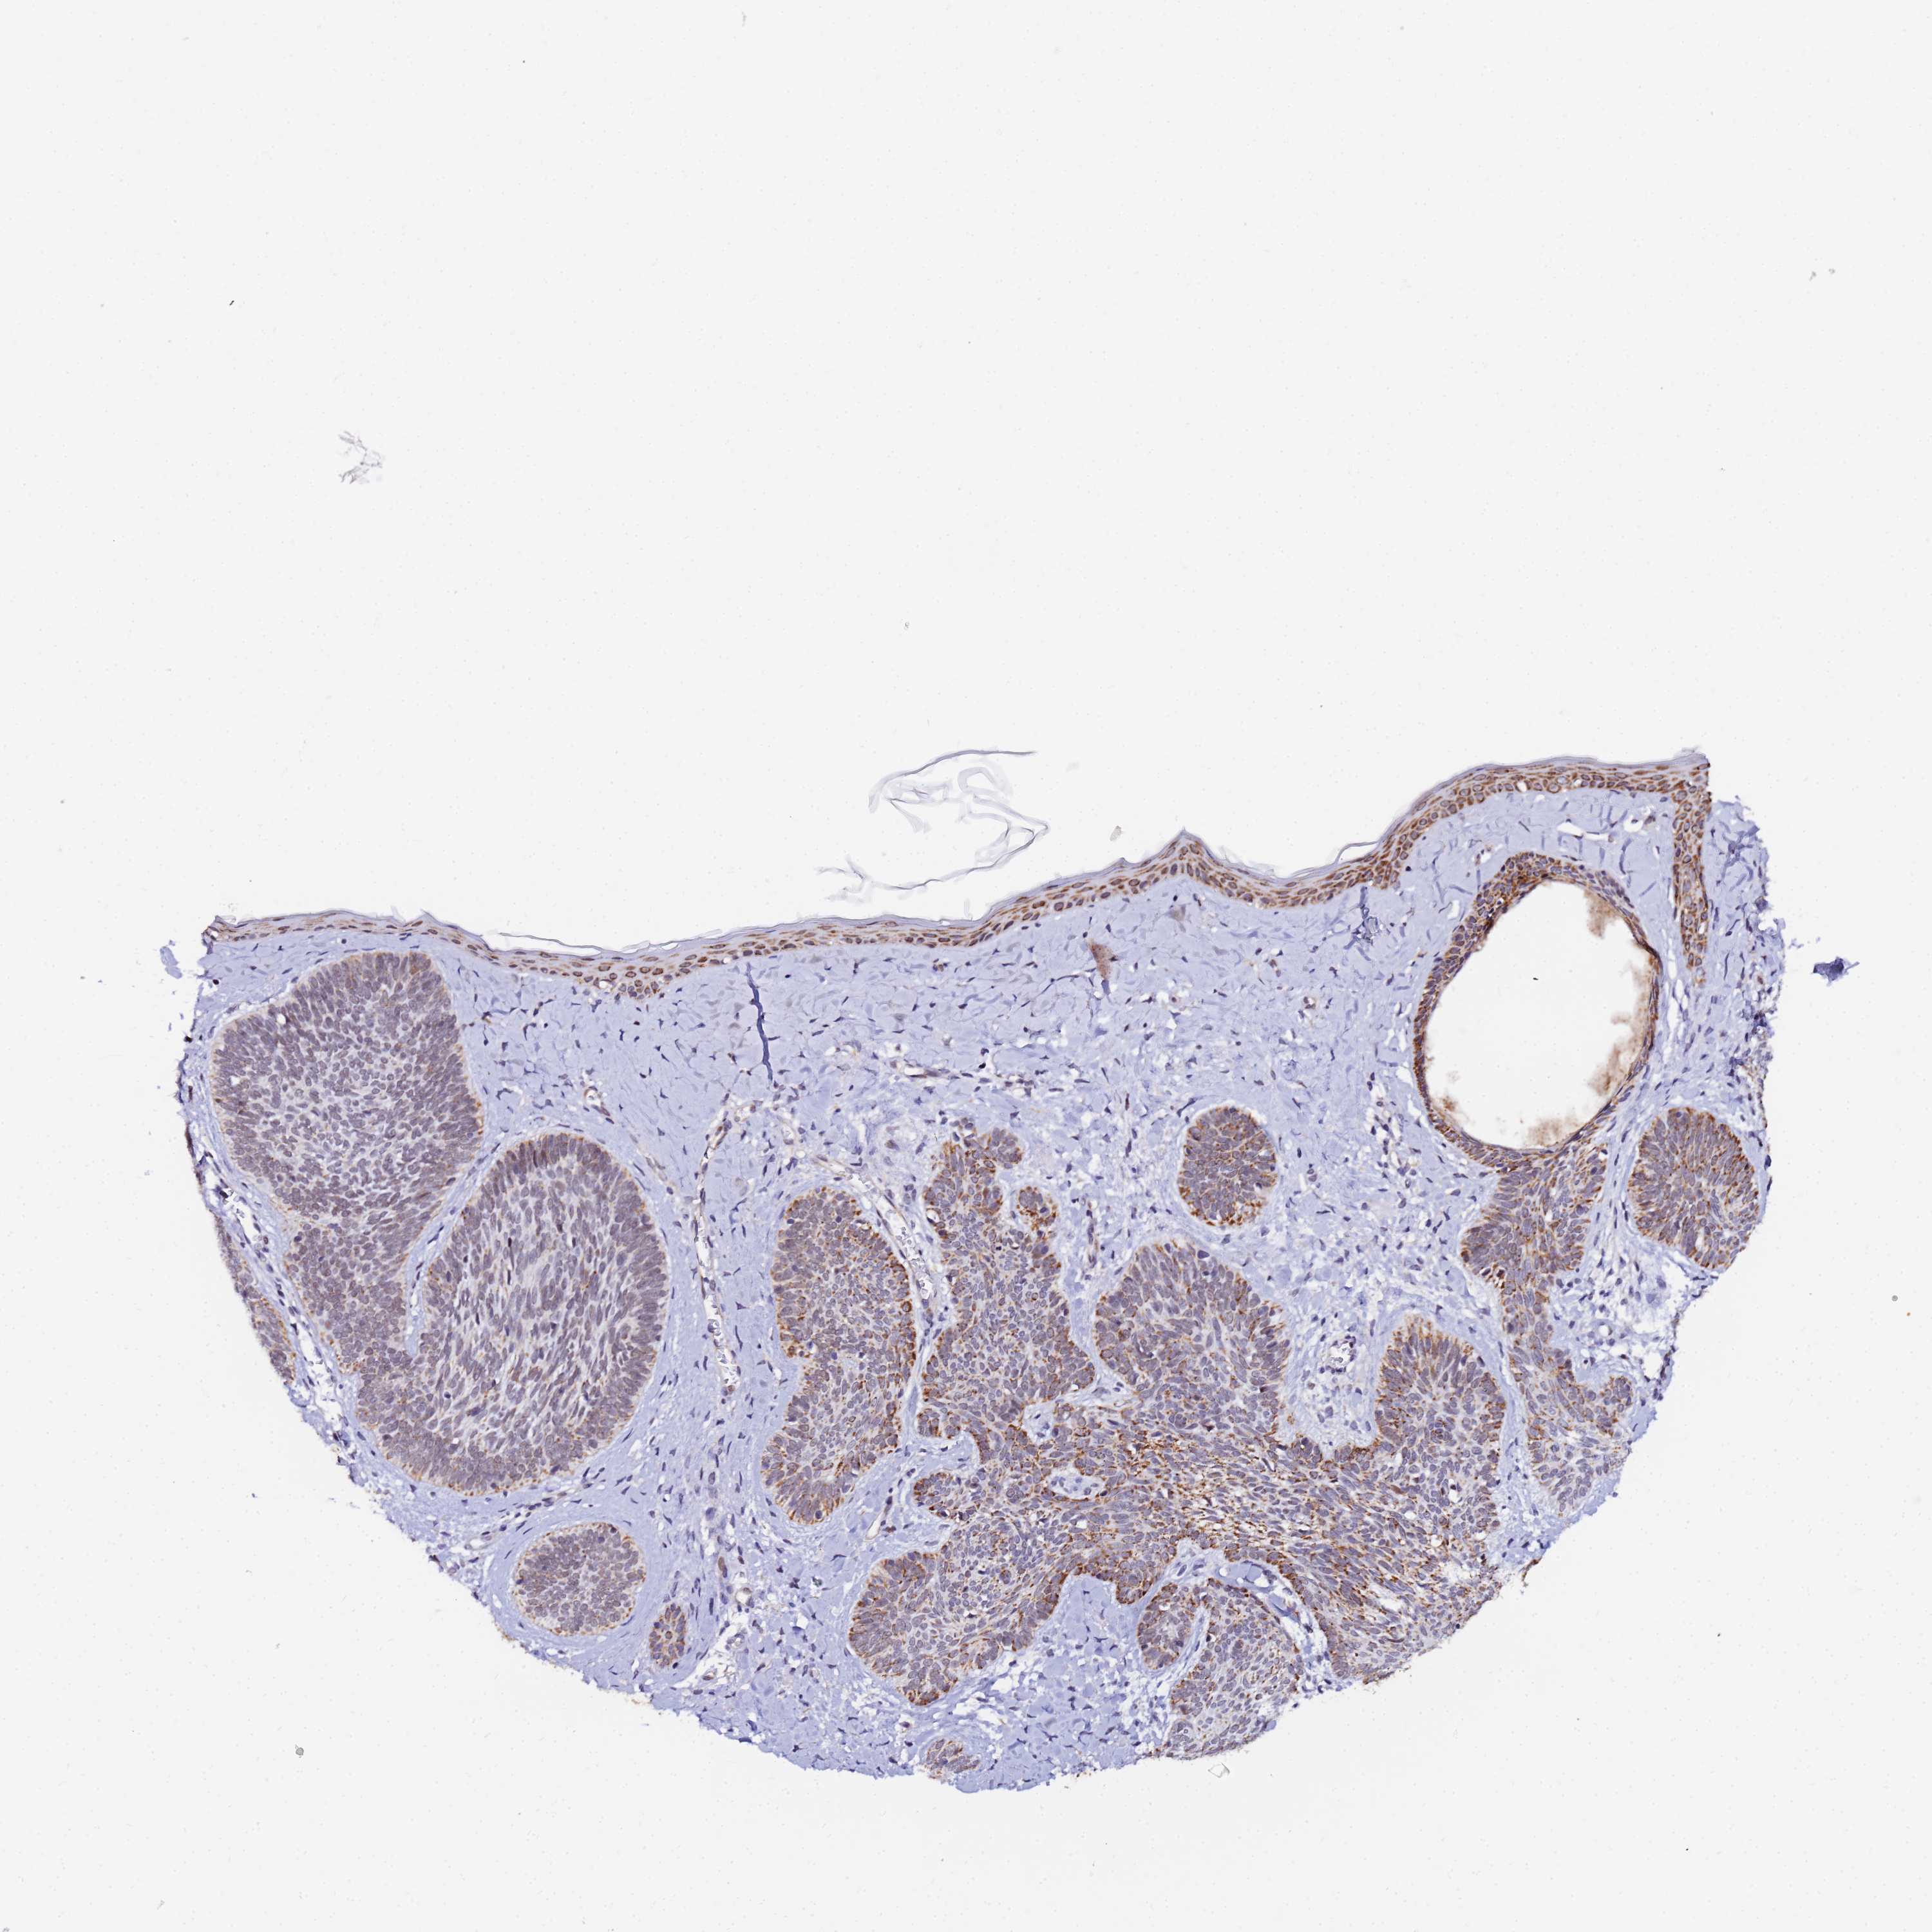

Basal cell and squamous cell cancer

SKIN CANCER - Protein expressioni

A mouse-over function shows sample information and annotation data. Click on an image to view it in a full screen mode. Samples can be filtered based on level of antibody staining by selecting one or several of the following categories: high, medium, low and not detected. The assay and annotation is described here.

Antibody stainingi

Antibody staining in the annotated cell types in the current human tissue is reported as not detected, low, medium, or high, based on conventional immunohistochemistry profiling in selected tissues. This score is based on the combination of the staining intensity and fraction of stained cells.

Each image is clickable and will lead to virtual microscopy that enables deeper exploration of all samples and also displays staining intensity scores, fraction scores and subcellular localization as well as patient and tissue information for each sample.

Antibody HPA043491

Staining

High

Medium

Low

Not detected

Intensity

Strong

Moderate

Weak

Negative

Quantity

>75%

75%-25%

<25%

None

Location

Nuclear

Cytoplasmic/membranous

Cytoplasmic/membranous,nuclear

Basal cell carcinoma